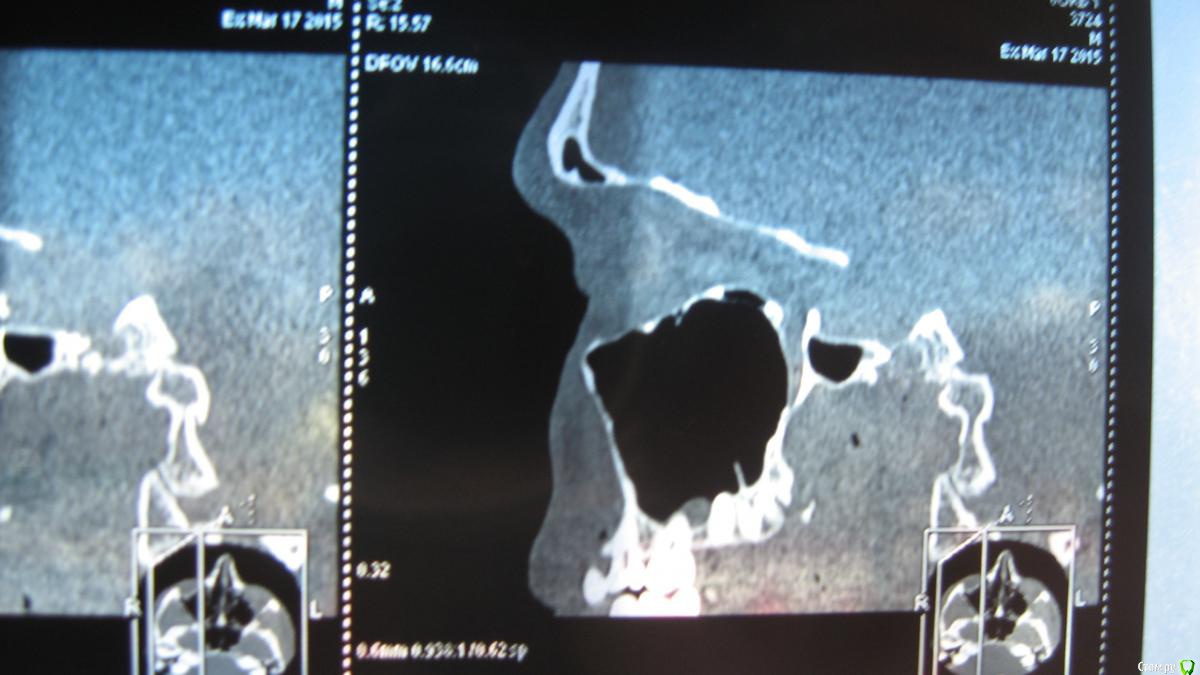

sasha35 Опубликовано 21 марта, 2015 Поделиться Опубликовано 21 марта, 2015 Здравствуйте. Осенью 2014 года лечил 4 зуб вверху. На 2 день после установки пломбы была боль, которая прошла через несколько дней. Со временем обнаружил, что больно нажимать на верхушку корня. Сам по себе не болит.Сделал снимок зуба, сходил к стоматологу. Он сказал, что плохо запломбирован канал. Я отказался вскрывать зуб. Сейчас появилась необходимость сделать СКТ ППН (для испр. носовой перегородки). Обнаружена киста в/ч пазухи, с той стороны где этот зуб(7*8мм) Сделал панорамный снимок челюсти, пошел к челюстно-лицевому хирургу. Он на снимке ничего не нашел. Тоже сказал, что зуб плохо запломбирован и возможно идет воспаление. Кисты на снимке нет. Может такое быть, на СКТ киста есть, а на рентгене нет? Выходит либо кистане связана с зубом, либо на СКТ воспаление показало как кисту? К кому мне обращаться? Ссылка на комментарий

sasha35 Опубликовано 22 марта, 2015 Автор Поделиться Опубликовано 22 марта, 2015 СКТ и рентген зуба. Панорамного снимка нет. Ссылка на комментарий